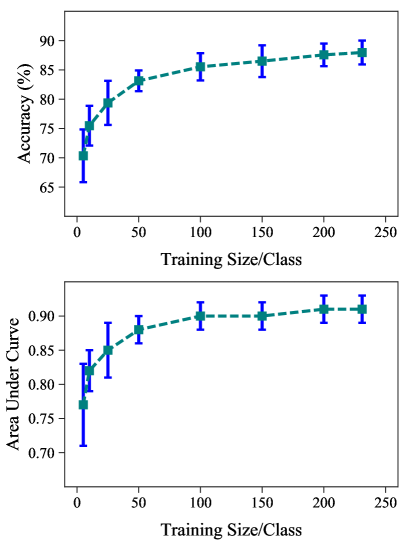

Having around 600 images for training a network is not sufficient. We wanted to see how does the mean accuracy and the standard deviation vary as we change the number of training examples. Since averaging over multiple train-test splits gave a robust classification accuracy and other figures of merit, we used this classification process to identify the deviation of the result as a function of the number of training images. The results are shown in Fig. 4. As expected, for both accuracy and AUC, the mean is lower and deviation is higher for less than 50 training example per category. As the number of example increases, the mean increases and the deviation decreases coming to a saturation at about 200 images.